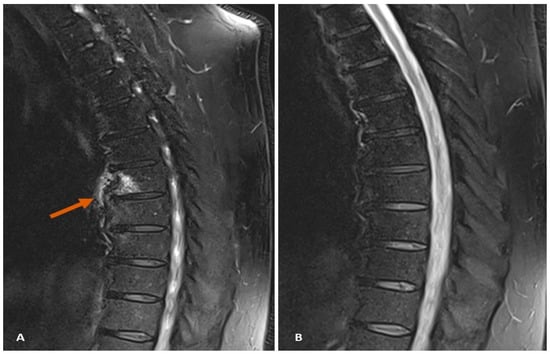

7.1. Case Study 1